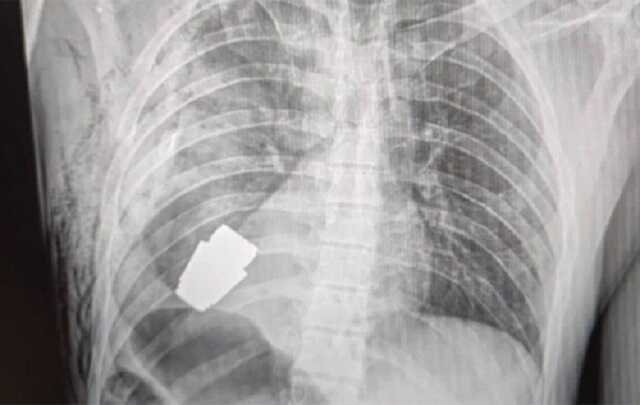

Українські хірурги провели унікальну операцію пораненому військовослужбовцю. Вони дістали з тіла воїна гранату ВОГ, що не розірвалася.

За її словами, українські хірурги змогли провести дійсно унікальну операцію – і дістали з тіла пораненого воїна гранату ВОГ, що застрягла у нього в ділянці серця і дивом не вибухнула.

"Операція проводилася одним із найдосвідченіших хірургів ЗСУ – Андрієм Вербою без електрокоагуляції, оскільки граната могла детонувати у будь-який момент. Оперативне втручання пройшло успішно, а пораненого військовослужбовця було відправлено на подальшу реабілітацію та відновлення", – зазначила чиновниця.

Вона також опублікувала світлину хірурга, який проводив операцію, та рентген-знімок, на якому видно гранату в тілі воїна.